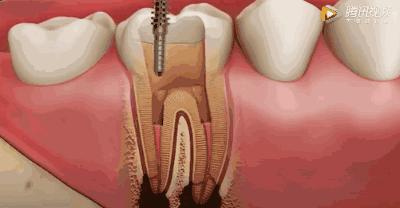

用根管器械在牙髓上做活塞运动

将坏的牙髓清理干净。目的是去净根管壁上的感染物,通过根管器械的切削作用去除感染的牙本质并清理根管壁细菌以利于根管充填。